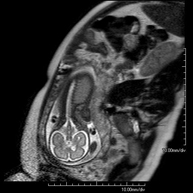

Prueba diagnóstica no invasiva que consiste en la obtención de imágenes de alta definición anatómica de la pelvis mediante el empleo de un campo electromagnético y ondas de radio (con un emisor y un receptor). No utiliza radiación ionizante. Se realiza para estudiar patologías del útero, del ovario, de las trompas y la vagina, ya sean de origen tumoral, inflamatorio o vasculares. Además permite valorar les estructuras adyacentes localizadas en la pelvis, identificando sus alteraciones. A veces requiere el uso de contraste intravenoso (Gadolinio) para caracterizar las lesiones. - RM Pelvis masculina

Prueba diagnóstica no invasiva que consiste en la obtención de imágenes de alta definición anatómica de cualquier región del cuerpo mediante el empleo de un campo electromagnético y ondas de radio (con un emisor y un receptor). No utiliza radiación ionizante. Se realiza bajo sedación con la colaboración del equipo de Anestesia. En los pacientes pediátricos es de gran ayuda porque permite realizar exploraciones sin artefactos de movimiento (lactantes, niños de corta edad, etc. en los que la situación clínica lo requiera). - RM Fetal

Prueba diagnóstica no invasiva que consiste en la obtención de imágenes de alta definición anatómica del feto en la mujer gestante mediante el empleo de un campo electromagnético y ondas de radio (con un emisor y un receptor). No utiliza radiación ionizante. Se puede realizar a partir de la semana 12 de gestación, siendo segura tanto para el feto como para la madre. Se utiliza en el caso de sospechar alguna anomalía congénita morfológica. - RM Muscular